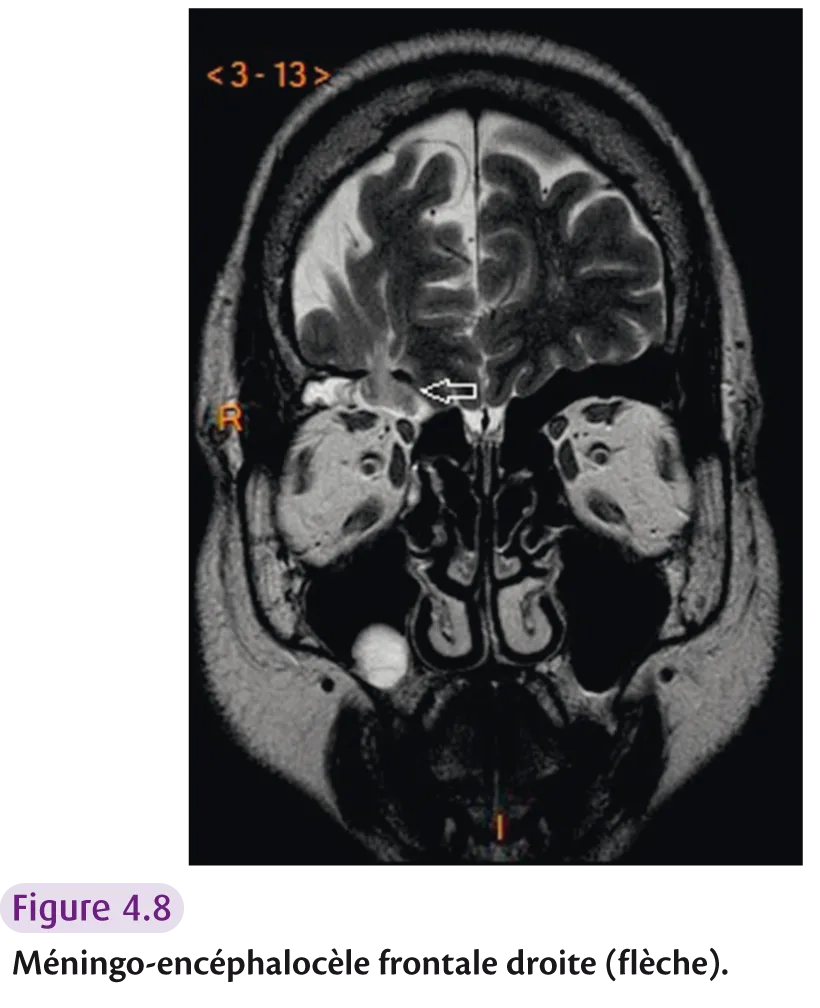

Risque de brèche ostéodurale : – déhiscence du toit de l’ethmoïde ; – asymétrie du toit de l’ethmoïde > 2 mm ; – insertion du processus unciné sur le cornet moyen; – déhiscence osseuse de la base du crâne avec méningoencéphalocèle (figure 4.8).

Fig 4.8